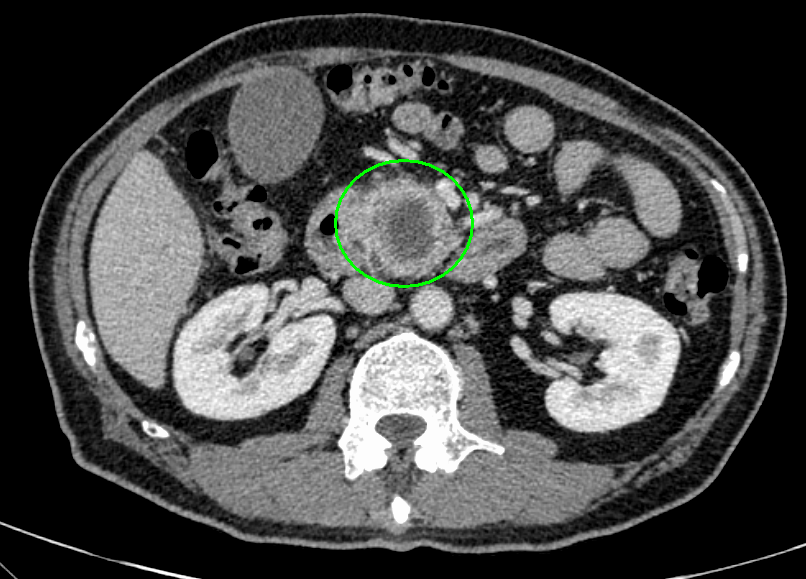

- 造影CT

術前シミュレーション画像(CT画像)